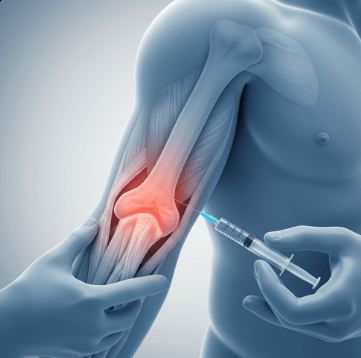

✅ 주사 치료 - 스테로이드 주사로 염증 감소 (3-6개월 효과)